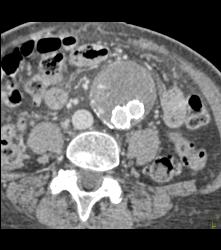

CTA of Iliacs With Auto-bone Removal